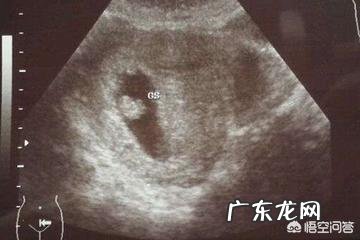

怀孕多久才会有胎心?如果您的月经周期特别规律,是30天的话,理论上一般42天也就是6周就有可能会看到胎心,但也有部分的孕妈妈需要在7周到8周 。

我朋友第一次做妈妈,用试纸测了双杠后,就迫不及待地想要看宝宝是不是发育健康 。因为这个宝宝是她期待已久的了 。那时候估计也就30多天,到了医院,医生给照了B超,说只看到了孕囊 。到了6周,她又去医院做了B超,但是没看到胎心胎芽,这把我朋友给愁的,后来到了8周多,她又去了医院,这回好了,孕囊,胎心胎芽都可以看见了,这下她也放心了,可就确定这个是否健康怀孕,她就做了三次B超 。

如果孕6周时做B超没有胎芽胎心的话,化验血孕酮值及HCG值看情况,如果是超过了8周,B超还不见胎芽和胎心的那么就要考虑胎儿不良妊娠 。

如果月经周期规律,停经周数与孕周符合,那么原始胎心一般在孕5周后形成,最早孕5周可以通过经阴道B超探及点状胎心 。

随着胚胎的发展,胎心也逐渐成熟,绝大多数的孕妈在六七周都能看到胎心,孕八周已经形成胎儿的小心脏了 。

胎心的出现代表着宝宝有了生命,根据停经的天数结合胎心出现的时间,也能侧面判断宝宝是否发育良好 。下面跟大家细细说一下胎心的事 。

对于月经规律的女性来说,在停经6周左右就可以在彩超情况下看见胎心以及胎芽 。很多女性会有这样的疑问,以及40多天了去医院检查为什么还没有胎心及胎芽,发育不好吗?这孩子是不是不能要了?不是的 。胎心出现较晚或是没有胎心的因素有很多,其中比较常见就是排卵的推迟,导致形成受精卵时间的推迟,同时出现胎心胎芽的时间也会比6周要晚一些 。还有一个原因就是发育不好,这也是导致迟迟不出现胎心的原因,早期胚胎质量的问题,比较直观的表现就是没有胎心的出现,还有就是出血情况的发生 。这两种情况是导致停经6周不出现胎心的原因 。在这里需要强调的一点是,如果没有出现胎心以及胎芽,不能立即拿主意说做人流术放弃这个宝宝,建议咨询医生的建议以及去上级医院就诊 。